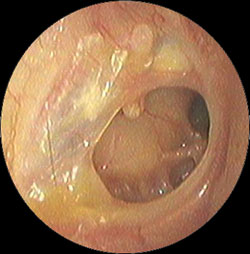

・鼓膜の内側に褐色の液体の貯留を認める

などの症状がでてきます。